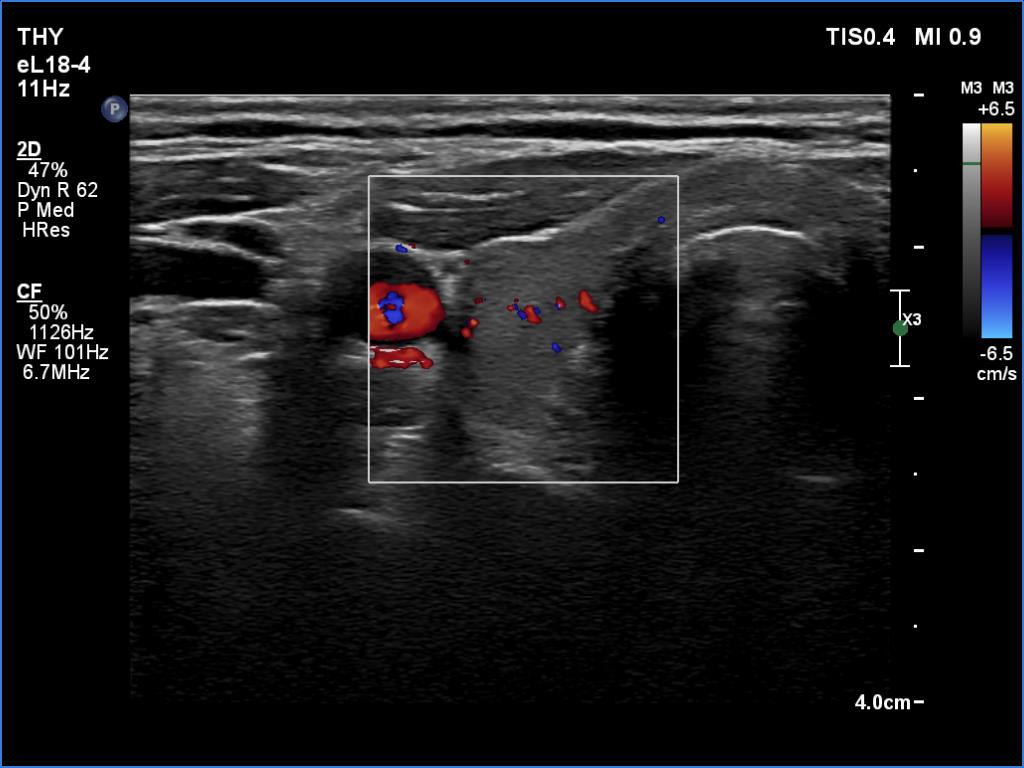

Right lobe, longitudinal scan

Right lobe, transverse scan, color Doppler method. The vascularization is average.